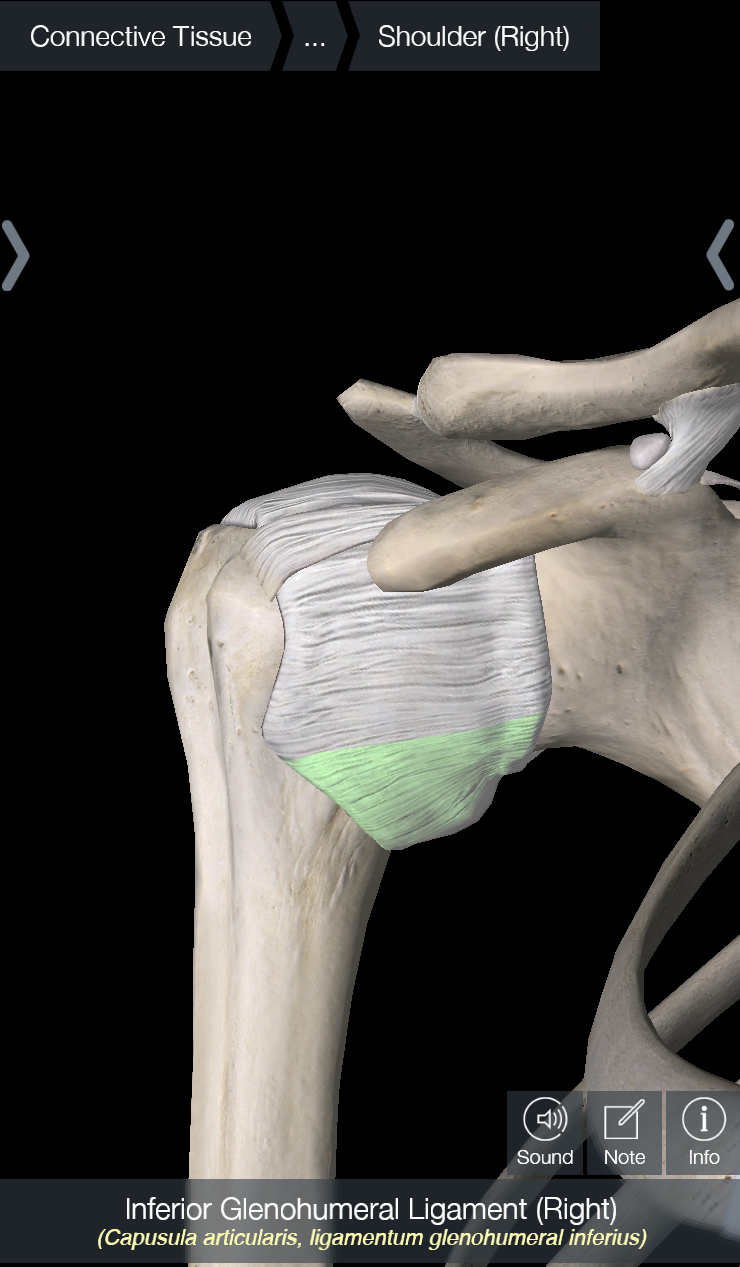

The shoulder joint – also known as the glenohumeral joint – is a ball and socket joint, with a piece of connective tissue called the labrum that surrounds the socket to make the joint more stable. The muscle that is most likely to be torn in an Americana is the subscapularis, which is one of the 4 muscles of the rotator cuff and crosses in front of the shoulder joint. In terms of ligaments, there is a capsule that surrounds the shoulder joint; this can be thought of as a large piece of tissue that surrounds the joint with several areas that are thickened throughout; these are considered ligaments. Of these ligaments – i.e. the ligaments contained within the capsule of the shoulder – the one we care about the most is the inferior glenohumeral ligament (IGHL). In addition, the coracohumeral ligament, which attaches from the front of the scapula to the ball of the shoulder joint, is also important.

In all the pictures below, we are looking at the shoulder from the front. In picture 1, I have removed everything except for the shoulder capsule. In picture 2, I have highlighted the IGHL, which is one of the most stressed ligaments in the shoulder with an Americana. You can imagine that if someone is rotating your shoulder upwards, that will cause this ligament to rotate upwards as well, making it the main part of the capsule being stressed. In picture 3, I have rotated the picture about 60 degrees and highlighted the coracohumeral ligament. And last but not least, in picture 4 I have highlighted the subscapularis.